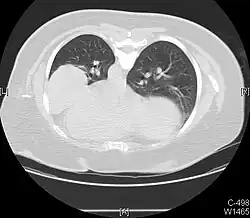

Masses

Masses such as tumors can also cause compression and displacement of mediastinal structures. There are various mediastinal tumors, and they are classified by their location in the chest. Notable examples include germ cell tumors and lymphomas.[12] Teratomas are a class of germ cell tumors that arise in the chest due to failure of germ cell migration during development. They can expand to large sizes and cause hemoptysis and pleural effusion. Radiographic features of teratomas typically include fluid and fat but also muscle, teeth, and bones inside the mass.[13]